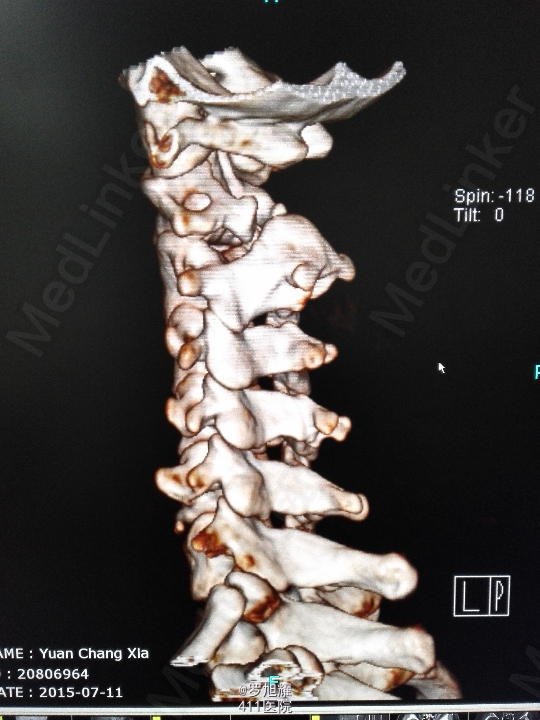

右侧躯体麻木1年,右上肢及下肢麻木2月余。 查体:颈椎活动受限,右上肢肘关节以远痛温觉减退,右侧胸4平面以下痛温觉及触觉减退,四肢肌力尚可,右侧霍夫曼征阳性,右侧上下肢所有腱反射亢进。 颈椎X线示:颈2椎板棘突缺如,颈3棘突肥大增高。 颈椎CT示:颈2椎板棘突缺如,颈3棘突肥大增高,颈2/3椎间盘突出,左侧颈2残留部分椎板进入椎管。枢椎齿突增生,寰枢关节退变。 颈椎MRI示:颈2/3椎间盘突出,左侧颈2椎板进入椎管,颈髓受压变性。

查体:颈椎活动受限,右上肢肘关节以远痛温觉减退,右侧胸4平面以下痛温觉及触觉减退,四肢肌力尚可,右侧霍夫曼征阳性,右侧上下肢所有腱反射亢进。 颈椎X线示:颈2椎板棘突缺如,颈3棘突肥大增高。 颈椎CT示:颈2椎板棘突缺如,颈3棘突肥大增高,颈2/3椎间盘突出,左侧颈2残留部分椎板进入椎管。枢椎齿突增生,寰枢关节退变。 颈椎MRI示:颈2/3椎间盘突出,左侧颈2椎板进入椎管,颈髓受压变性。